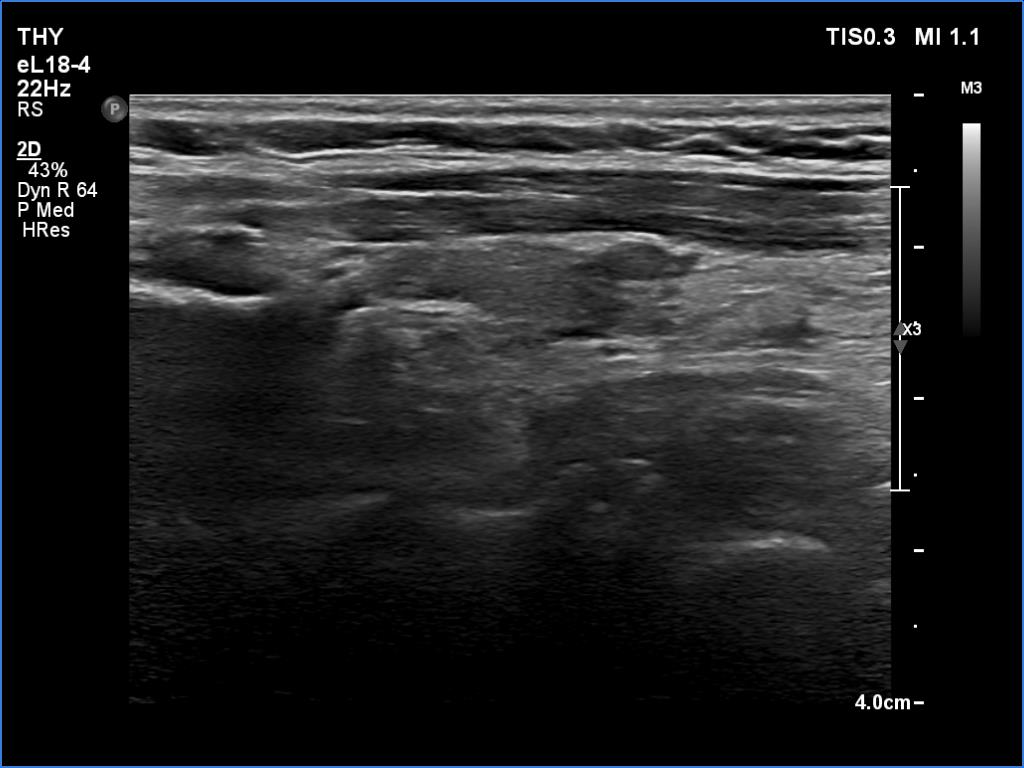

First examination (first row of images):

Ultrasonography. The thyroid was minimally hypoechoic. There was a small, discrete lesion in the upper pole of the right lobe. The left lobe had a larger and several tiny hypoechogenic lesions. The large lesion presented partly blurred, partly lobulated margins.

Cytology was performed from the large hypoechoic lesion in the left lobe and resulted in subacute, de Quervain's thyroiditis.